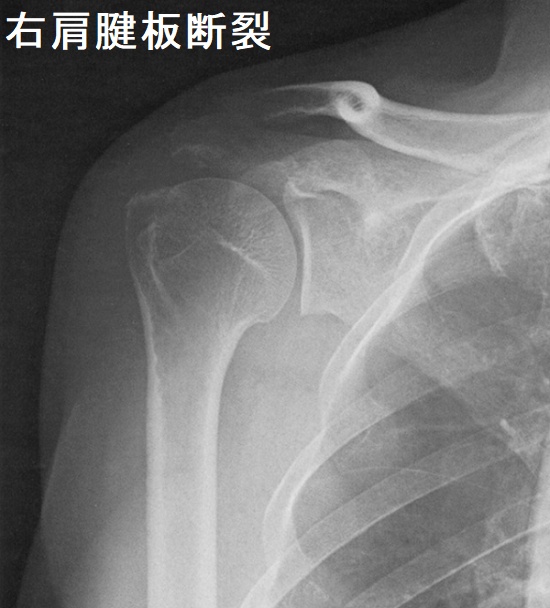

中高年に好発する肩腱板断裂は、重いものを持ち上げた時などに発症。突然の肩痛で始まり、最初は動作時の痛み(動作時痛)、次第に安静時痛と夜間痛も出現します。ある一定の肢位で疼痛が増強する有痛弧徴候、その肢位を保持できない腕落下徴候を認めます。

近年、肩腱板断裂の発生率が増加しています。当然ながら、肩腱板腱には甲状腺ホルモン受容体が存在し、腱の代謝と維持に関与しています。肩腱板断裂で関節鏡手術や小開放手術を受けた患者は、男女ともに高頻度で甲状腺疾患を持っていたとする報告があります。(Muscles Ligaments Tendons J. 2014 Nov 17;4(3):309-14.)

| 年齢(歳) | 女性(%) | 男性(%) |

|---|---|---|

| 20–40 | 50.00 | 14.81 |

| 40–60 | 56.44 | 19.3 |

| 60–80 | 63.6 | 22.67 |

| 80-90 | 27.27 | 0.00 |